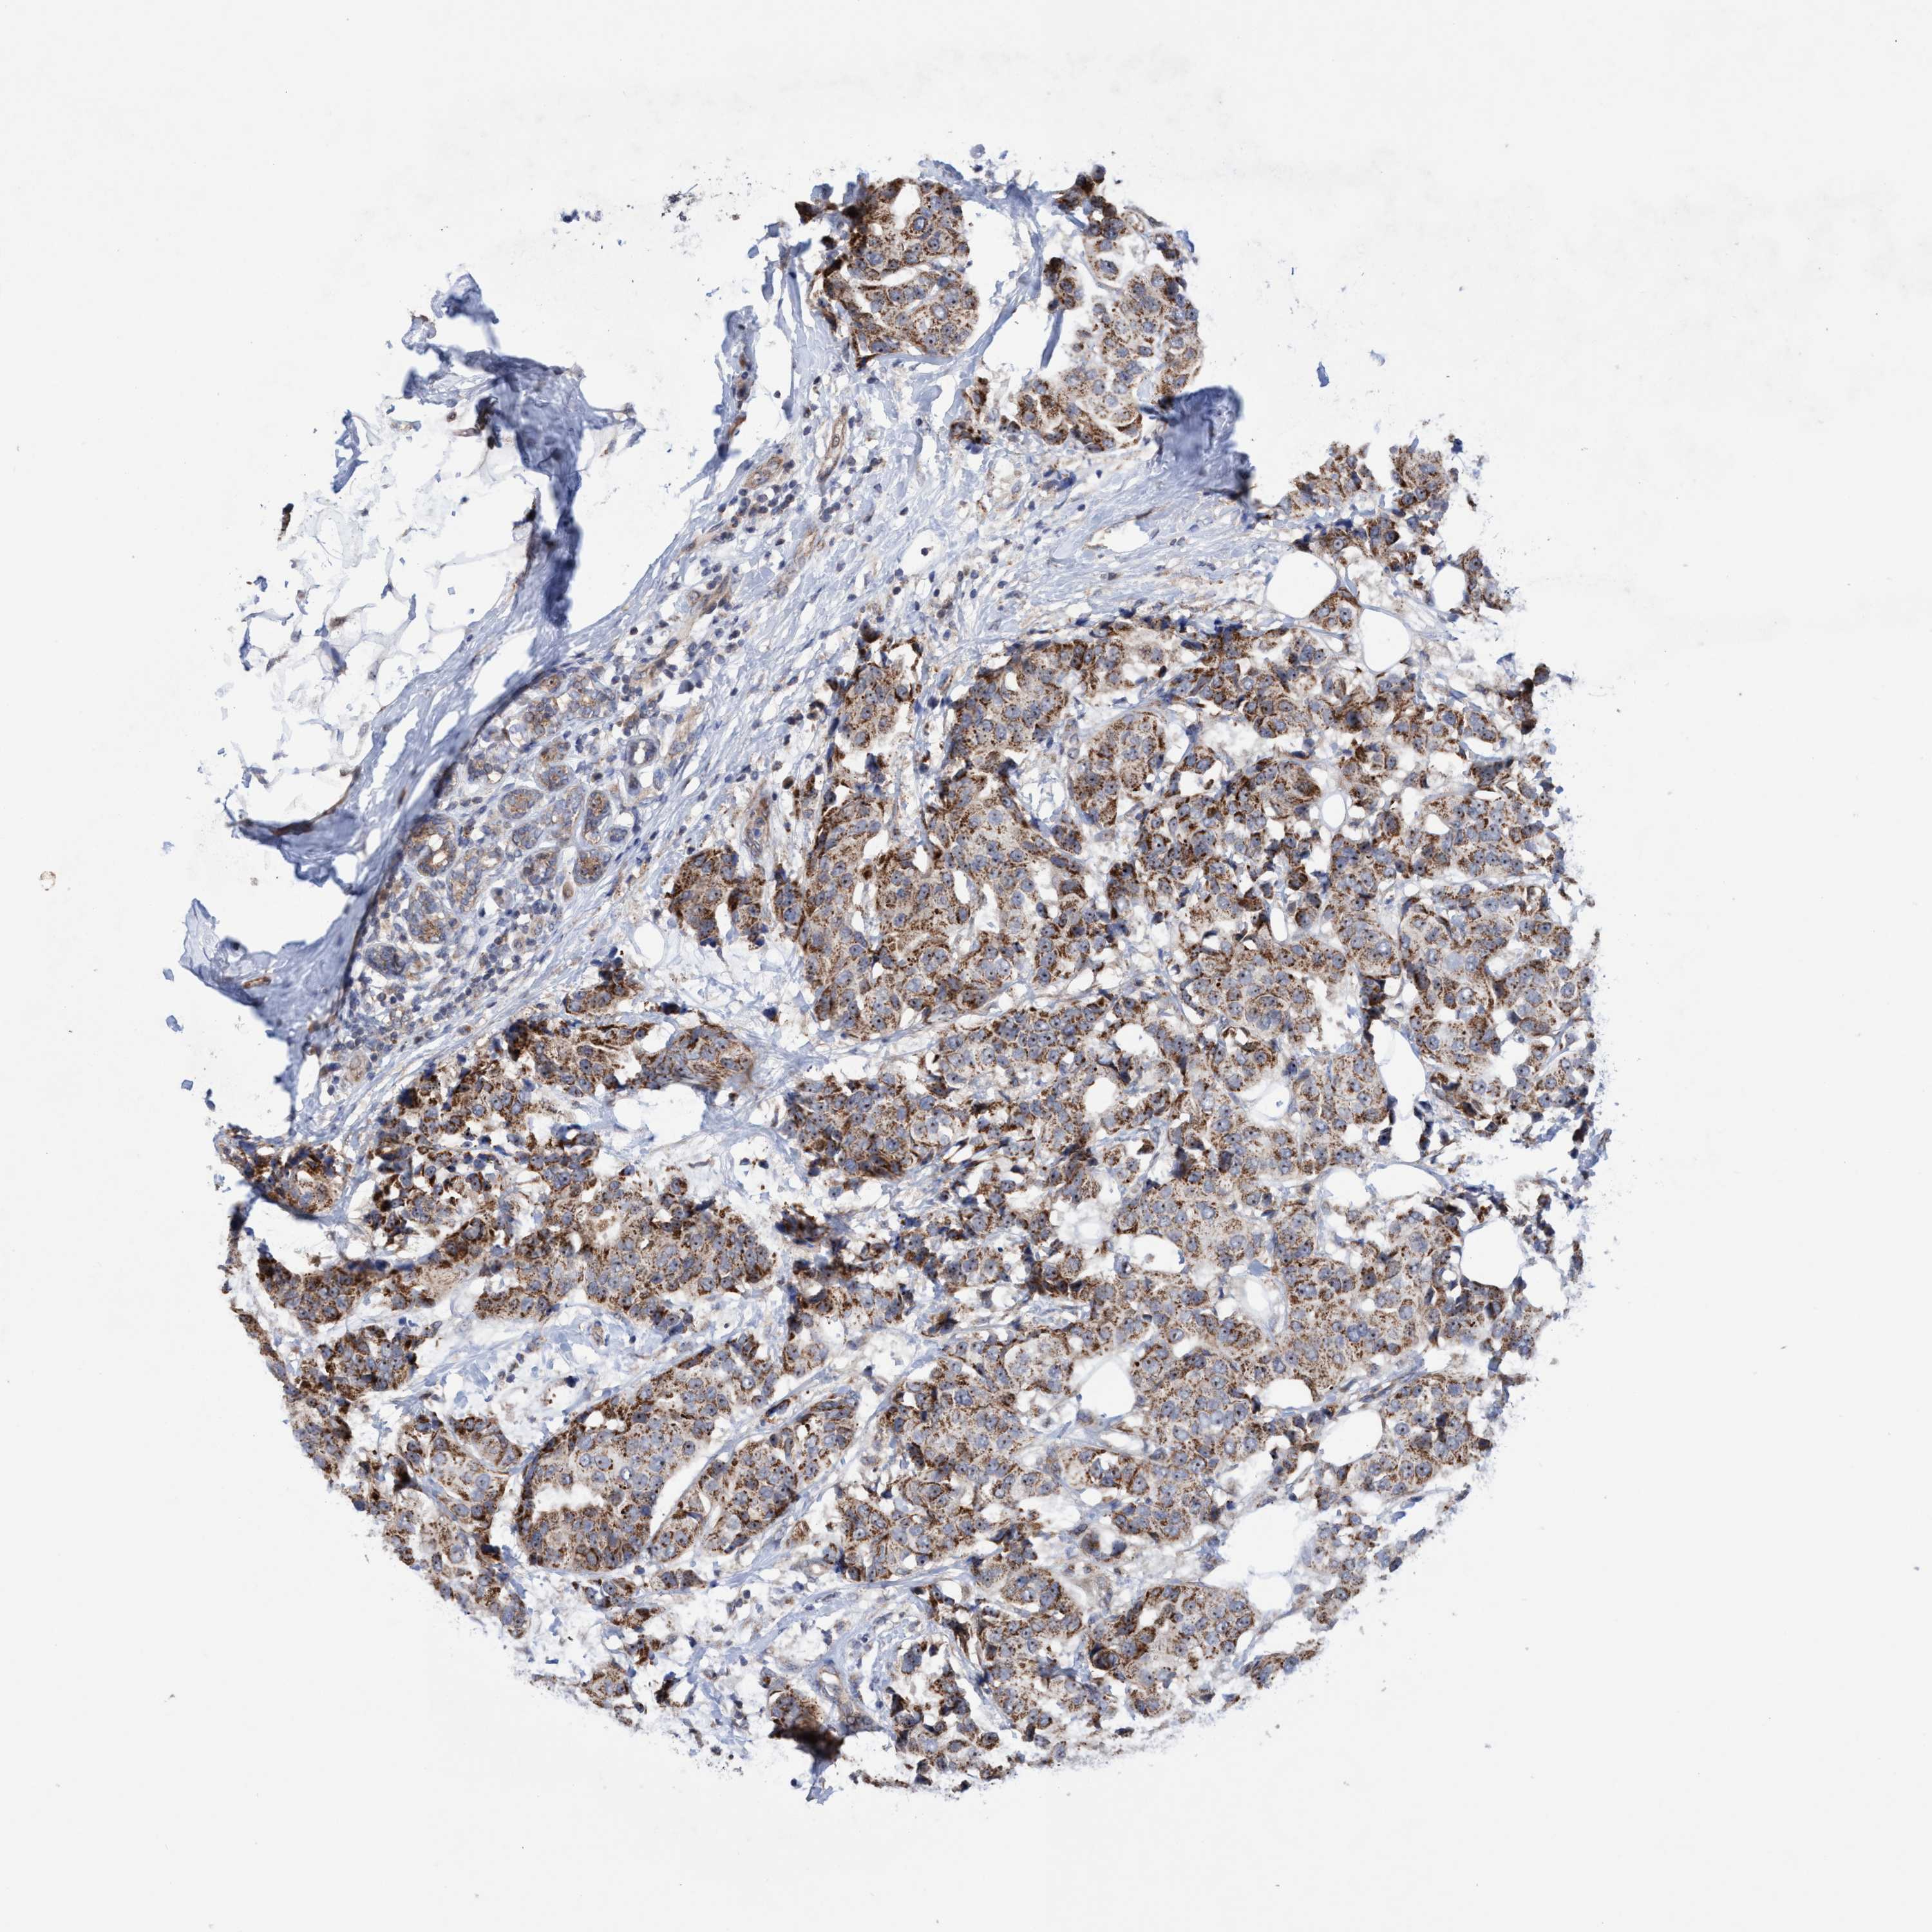

CANCER BREAST CANCER Show tissue menu

BRCA TCGA BRCA VALIDATION PROTEIN EXPRESSION